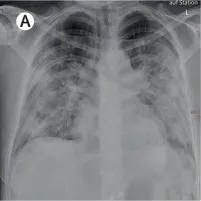

部分患者存在肺功能障碍

研究者对 319 名患者进行了肺功能测试、高分辨的胸部 CT 和超声检查。结果表明,部分患者存在肺功能障碍,且比例与患病严重程度相关——住院时需要呼吸机等设备的患者中,后续出现了肺功能障碍的有 56%;在住院时需要吸氧的患者,这一比例为 29%;无需吸氧患者中,这个比例则为 22%。

新冠肺炎影响患者的肺功能 | Lancet